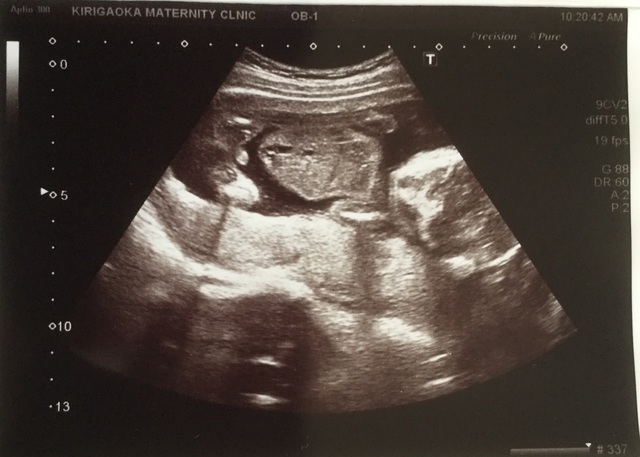

18週1日(18w1d・男の子)|はーちん さん(27歳)

エコー写真撮影時のエピソード:

性別が8割男の子だと分かったときです。毎回楽しみにしているエコー。4週間に1度の検診が楽しみであり不安でもあり毎回ドキドキしています。

1番はっきりと顔が見えたエコー写真で、これ以降下を向いていたり横を向いていたりとなかなかお顔を見せてくれません。なので産まれてくるのがもっと楽しみです!